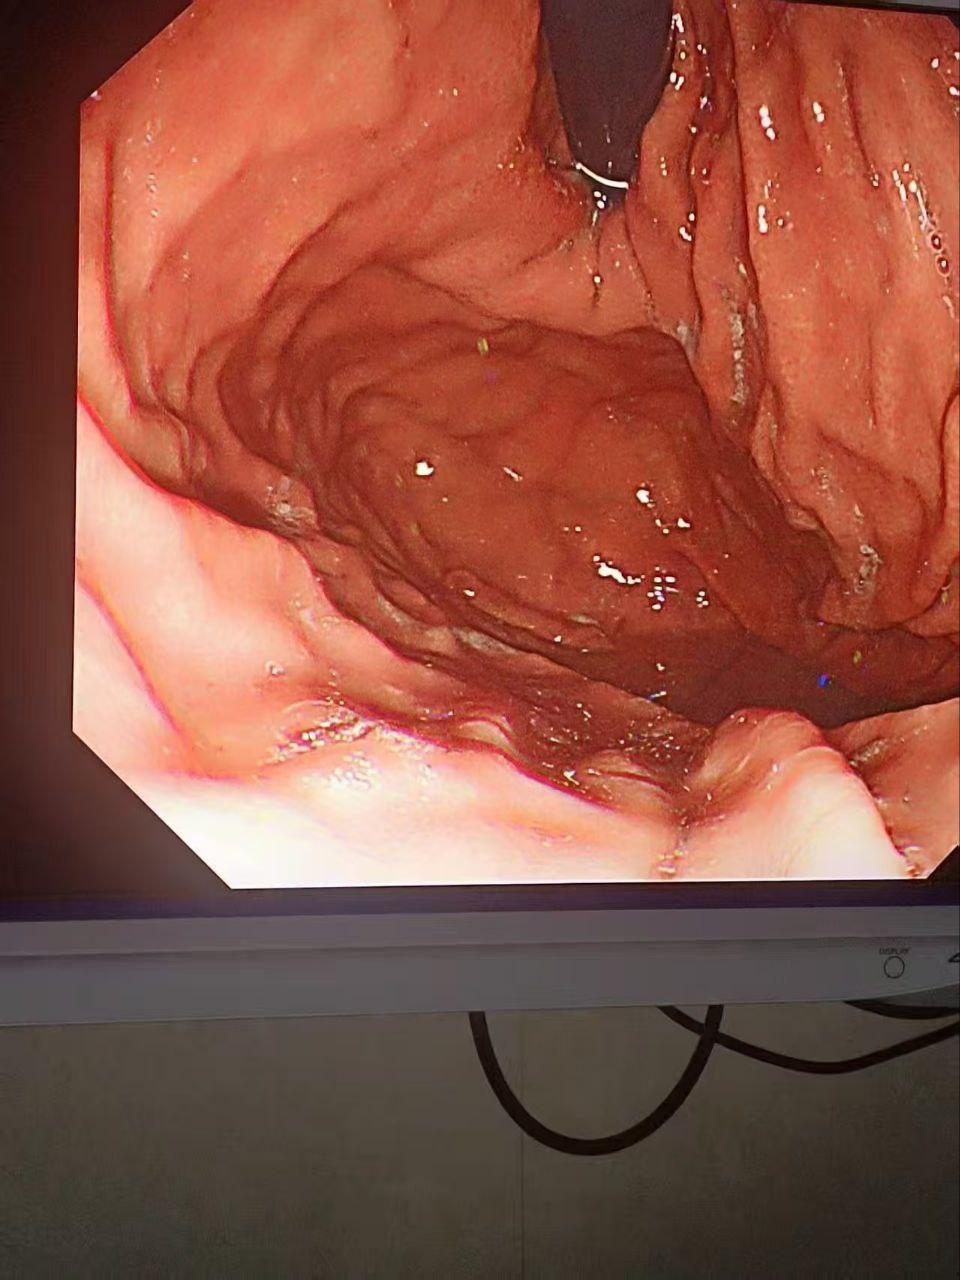

正文 金主酒吧消费巨款,陪酒女为博金主一笑,酒后拳交,玩大了,金主爸爸手上戒指卡里面! admin V管理员 /2024-11-17/1阅读/0评论 1117 文章最后更新时间2026年01月02日,若文章内容或图片失效,请留言反馈! 金主酒吧消费巨款,陪酒女为博金主一笑,脑子一热跟金主玩酒后抠屁眼,现场有姐妹看着,但不料还是玩大了,金主爸爸狂抠,不料戒指掉进屁股里找不到了,事后才发现顺着小肠进去了,你们有钱人玩的真花呀。#离谱 #吃瓜 #金主 #陪酒 #酒吧 #抠屁眼 #奇葩 #骚母狗